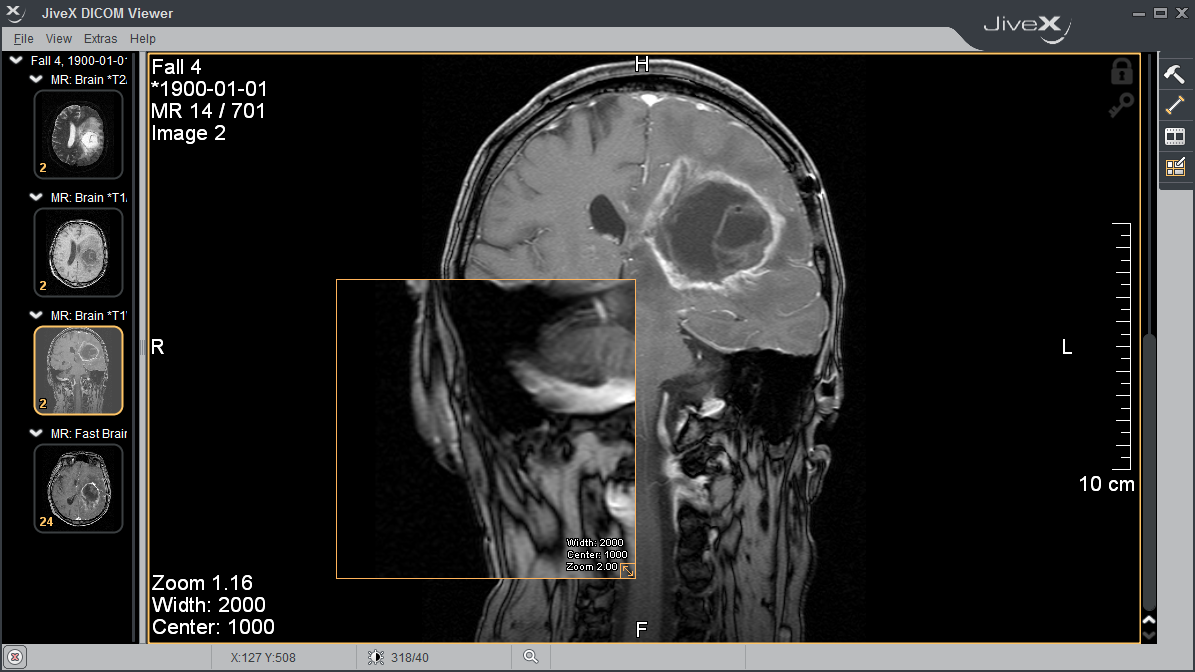

Лазерная камера для печати медицинских изображений на пленке стандарт dicom